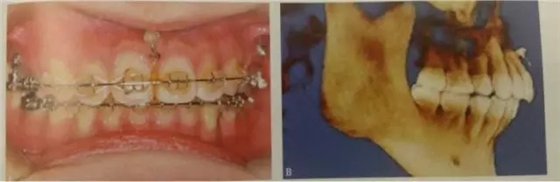

“壓低后牙

后牙區(qū)牙及牙槽過高引起的開合畸形、雙側磨牙長期缺失導致的對合牙伸長等情況,常需要對雙側后牙進行壓低處理。在這一方面,因為微種植釘能有效壓低后牙,有其顯著地優(yōu)勢。

頰側可以植于第二前磨牙和第一磨牙牙根間,第一磨牙頰側近遠中根、或第一磨牙和第二磨牙根尖之間。對于有些上頜合平面偏斜、單側后牙鎖結、個別后牙因對合牙缺失而伸長等患者,可以考慮單側后牙區(qū)植入微種植體。對于前牙開合畸形,下頜缺乏縱合曲線,spee曲線過于平坦,雙側后牙正鎖合等情況。